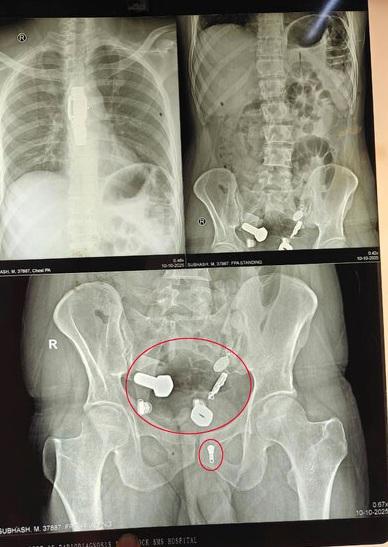

又一異食癖的誇張案例……英國《鏡報》等媒體報道,印度齋浦爾(Jaipur)一名34歲男子因劇烈腹痛、無法飲水進食,本月9日被家人送往醫院急症室就診。醫生替他做X光等檢查,驚見他食道裡竟卡著一隻手錶,大腸裡還有多塊鐵片、螺絲帽、螺絲、繩子、吊墜等物品,讓醫療團隊十分驚訝。

醫療團隊隨即進行長達3小時的緊急微創手術,先在男子腹部開一個小切口,再用儀器將男子食道和腸道裡的所有異物取出。